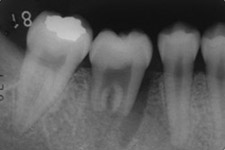

適切な条件がそろえば、歯の移植が可能です。歯の移植とは、治療することができない歯を抜いて、その場所へ本人の親知らずなどの歯を移す治療です。例えば、下のパノラマエックス線写真は18歳の男子です。右下の第一大臼歯が割れて痛みを伴って来院されました。この歯の保存できないと判断して、その歯を抜歯し,後ろにあるまだ生えていない親知らずをそこへ移植しました。移植の適切な条件とは、患者さん年齢が概ね40歳以下であること、口腔内に適切なドナー歯(主に親知らず)があること、移植歯(ドナー歯)と移植部位(受容側)の大きさが適合すること、などです。

治療前:第一大臼歯が割れてしまっていて治療することが困難です。